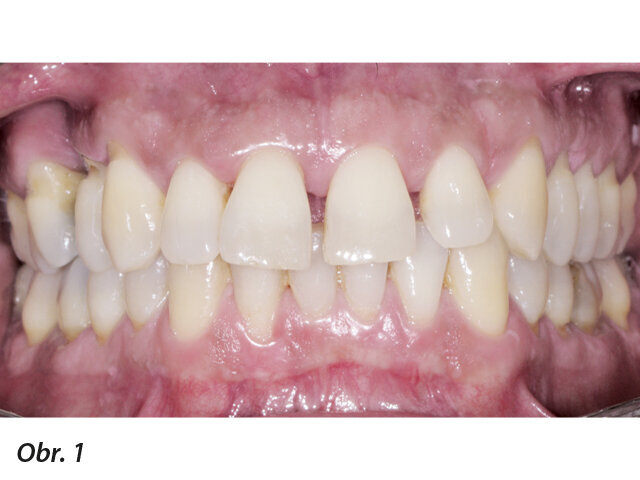

Obr. 1–5: Fotografi cká dokumentace počátečního stavu před parodontologickým ošetřením

49letý pacient přišel na naše oddělení se stížností na krvácení dásní a rozestupování frontálních zubů (obr. 1–5).